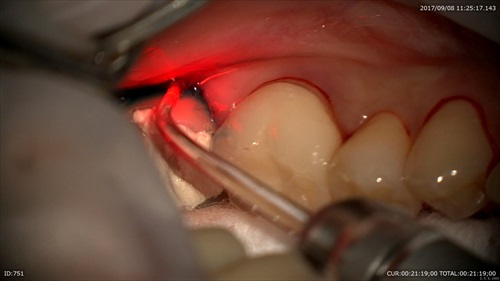

2:歯周病治療

マイクロスコープで研ぎます。70度。

デブライドメント